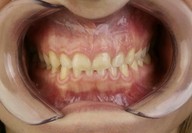

Mascherina in silicone trasparente e di compositi iniettabili: i protagonisti della Injectable technique

► Mock-up e pre-visualizzazione

Galleria fotografica